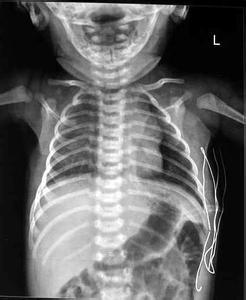

新生儿先天性膈疝(congenital diaphragmatic hernia,CDH)是由于胚胎时期膈肌闭合不全,至单侧或双侧膈肌缺陷,部分腹部脏器通过缺损处进入胸腔,造成解剖关系异常的一种疾病,分胸腹裂孔疝、食管裂孔疝和先天性胸骨后疝。